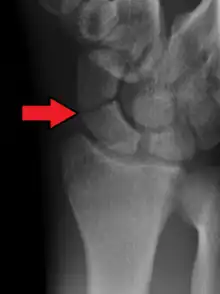

A subtle scaphoid fracture